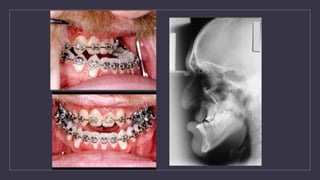

Orthodontic Treatment ofTransitional Dentition • The purpose the dentition adjacent to cleft has to be orthodontically repositioned to prepare the cleft side for the secondary alveolar bone graft • Preparing the maxillary arch for a bone graft (6-12 months) : 1. Bonded edgewise appliance 2. Supported with a maxillary expander quad helix expander

• 55.

Alveolar Bone Grafting •Primary Bone Grafting • Bone graft done at the time of primary cheiloplasty • Bone graft done during the first 2 years of life • Bone graft done prior to the eruption of the primary canine

• 56.

Secondary Bone Grafting •Done before eruption of the permanent canine • Usually when the root of the canine is 1/3 to 2/3 formed • Usually between ages 8-10 • In CLP dental age is usually behind chronological age

• 57.

Quadhelix to expandprior to ABG

• 58.

angle brackets tokeep roots away from cleft

Alveolar Bone Grafting 1.Provide bone for the eruption and/or orthodontic repositioning of teeth 2. Closure of oro-nasal fistulas 3. Support and elevation of the alar base 4. Stabilization of the pre-maxilla in bilateral cases 5. Provide continuity of the alveolar ridge

Alveolar Bone Grafting PreoperativeCleft Defect Postoperative Bone Graft

•Correction of anterior crossbite •Archexpansion Quad Helix Expansion screws Orthodontic Treatment For Permanent Dentition